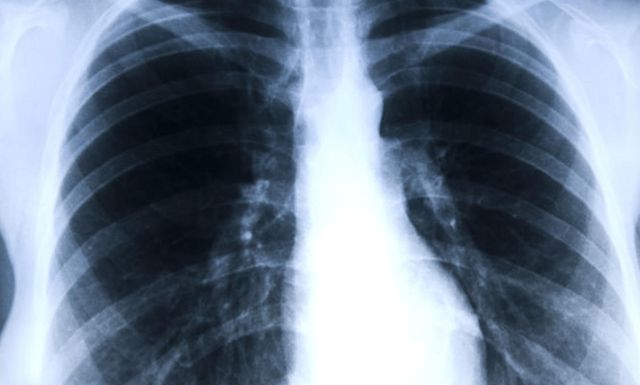

询问得知,崔大姐深信自己得了肺癌,因为她在体检中发现肺部有结节。她不敢来医院做进一步的检查,但最后在家人劝说的情况下,她别无选择,只能踏进医院。

事实上,根据崔大姐的影像检查结果,她自己所谓的肺癌,只是在右肺下叶发现了一个小结节。结节直径约1m,边缘清晰。此外,根据崔大姐自己的描述,她没有咳血、疲劳、发热等症状,但崔大姐是一名厨子,经常接触油烟,早上还经常伴有轻微咳嗽。

医生告诉她,大多数病人在体检中发现肺结节时,并无明显症状,且结节较小,表明在发病初期,良性病变的可能性很大。对直径小于1cm的小结节,病人只要后期积极治疗,定期复诊,改善不良生活习惯,极有可能使其逐渐减少,甚至消失。